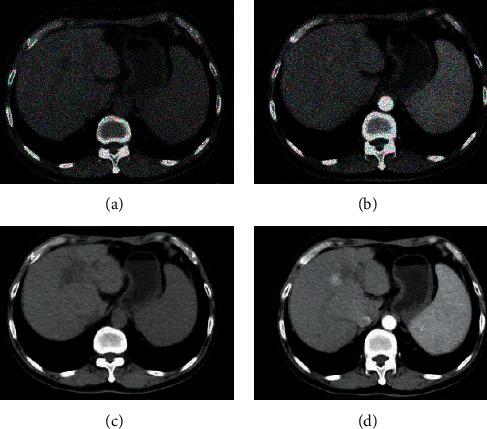

This study was to explore the application value of computed tomography (CT) images processed by intelligent algorithm denoising in the evaluation of humanized nursing in postoperative neuroendocrine hormone changes in patients with primary liver cancer (PLC). In this study, a simple-structured recursive residual coding and decoding (RRCD) algorithm was constructed on the basis of residual network, which can effectively remove artifacts and noise in CT images and can also restore image details and lesion features well. In addition, 60 postoperative patients with primary liver cancer were collected and divided into routine nursing control group (30 cases) and humanized nursing experimental group (30 cases). After a period of nursing, CT images based on intelligent algorithms were evaluated by determining the hormone content. The results showed that the focal necrosis rate (FNR) of the experimental group was 6%. The adrenocorticotropic hormone (ACTH) levels of 6 and 15 days after admission (T3 and T4) were 41.25 ± 3.81 pg/mL and 19.55 ± 1.72 pg/mL, respectively. The cortisol levels of days 6, 15, and 30 after admission (T3, T4, and T5) were 424.86 ± 16.82 nmol/L, 277.98 ± 14.36 nmol/L, and 241.53 ± 13.27 nmol/L, respectively. Estradiol levels were 53.48 ± 11.19 pg/mL, 41.64 ± 9.28 pg/mL, and 30.59 ± 8.16 pg/mL, respectively. Testosterone levels were 2.18 ± 1.14 ng/mL, 1.78 ± 1.03 ng/mL, and 1.42 ± 0.69 ng/mL, respectively. Self-Rating Anxiety Scale (SAS) scores were 40.24 ± 5.81 points, 36.55 ± 5.02 points, and 32.53 ± 4.8 points, respectively. There were 24 cases, 27 cases, 23 cases, and 21 patients who followed no smoking and drinking, taking medication on time, diet control, and self-monitoring. The scores of physical function, self-cognition, emotional function, and social function were 62.59 ± 6.82 points, 69.26 ± 8.14 points, 73.89 ± 6.35 points, and 66.88 ± 7.04 points, which were better than those of the control group in all aspects ( < 0.05). In short, the humanized nursing course can enhance the compliance of the patients after the surgery, improve the quality of life, and inhibit the anxiety and depression of the patients, so it showed a positive effect on the neuroendocrine hormones and the prognosis of the patients.